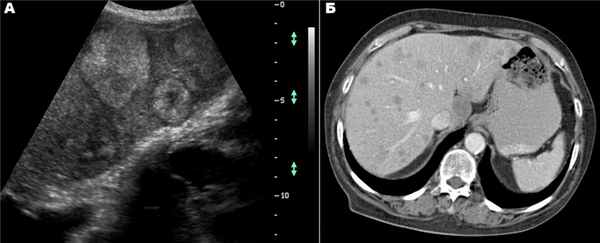

Выявление опухолей печени плода в антенатальном периоде происходит относительно нечасто, хотя в литературе встречаются описания различных типов новообразований. Они включают доброкачественные сосудистые опухоли (гемангиоэндотелиомы и гемангиомы), мезенхимальные гамартомы, аденомы и метастатические нейробластомы. Опухоли печени плода, выявляемые при эхографии, характеризуются разнообразными признаками и могут иметь солидную, кистозную (однокамерную и многокамерную) или смешанную (кистозно-солидную) структуру.

В целом эти характеристики бывают не специфичны для опухолей какого-либо определенного типа. Сочетание опухоли печени с водянкой плода свидетельствует о возможном наличии у него сердечной недостаточности, обусловленной артериовенозным шунтированием в сосудистой опухоли, такой как гемангиоэндотелиома или гемангиома. В некоторых случаях это возможно подтвердить с помощью допплерографии. Наличие кальцинатов в паренхиме печени плода может свидетельствовать о метастазах нейробластомы или о гемангиоме.

Несмотря на то что нам неизвестно о случаях антенатальной диагностики гепатобластомы, представляется вероятным, что она может выявляться у плодов, поскольку является наиболее часто встречающимся первичным злокачественным поражением печени в детском возрасте. Иногда в антенатальном периоде может выявляться кальциноз печени. Дифференциальный диагноз при наличии кальцинатов в печени плода включает в себя внутриутробную инфекцию, в частности токсоплазмоз или цитамегалию, опухоли печени, такие как метастазы нейробластомы, а также участки ишемического некроза печени.

При выявления изолированного кальциноза печени при исключении внутриутробной инфекции и неопластических процессов исход для плода часто бывает благоприятным. Необходимо проявлять внимание при определении локализации кальцинатов, поскольку их наличие в брюшной полости плода будет указывать на мекониальный перитонит.